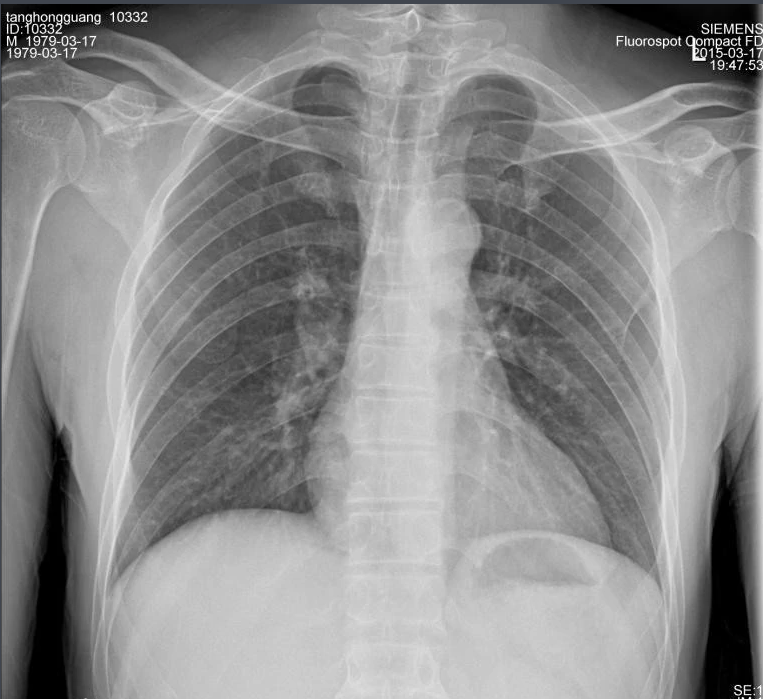

X射線,是一種頻率極高,波長極短、能量很大的電磁波。具有穿透性,但人體組織間有密度和厚度的差異,當(dāng)X射線透過人體不同組織時,被吸收的程度不同,經(jīng)過顯像處理后即可得到不同的影像。下面那我們來聊一聊關(guān)于X射線的三大特性分別是哪些。

X射線因其波長短,能量大,照在物質(zhì)上時,僅一部分被物質(zhì)所吸收,大部分經(jīng)由原子間隙而透過,表現(xiàn)出很強的穿透能力。X射線穿透物質(zhì)的能力與X射線光子的能量有關(guān),X射線的波長越短,光子的能量越大,穿透力越強。X射線的穿透力也與物質(zhì)密度有關(guān),利用差別吸收這種性質(zhì)可以把密度不同的物質(zhì)區(qū)分開來 。

X射線同可見光一樣能使膠片感光。膠片感光的強弱與X射線量成正比,當(dāng)X射線通過人體時,因人體各組織的密度不同,對X射線量的吸收不同,膠片上所獲得的感光度不同,從而獲得X射線的影像 。